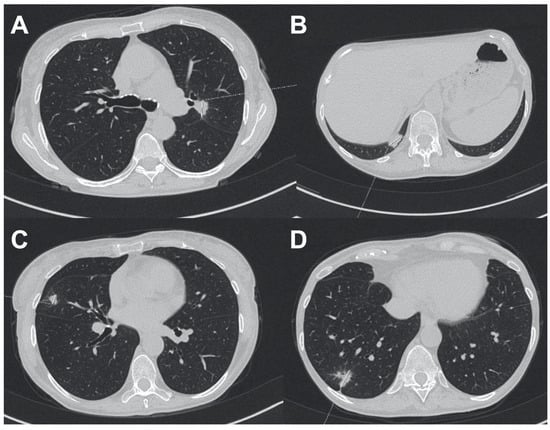

3. Case 2